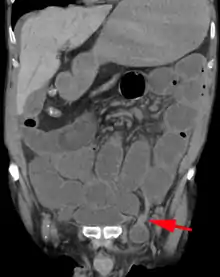

An inguinal hernia which contains part of the bladder. Bladder cancer also present.

When assessed by ultrasound or cross sectional imaging with CT or MRI, the major differential in diagnosing indirect inguinal hernias is differentiation from spermatic cord lipomas, as both can contain only fat and extend along the inguinal canal into the scrotum.[22]

On axial CT, lipomas originate inferior or lateral to the cord, and are located inside the cremaster muscle, while inguinal hernias lie anteromedial to the cord and are not intramuscular. Large lipomas may appear nearly indistinguishable as the fat engulfs anatomic boundaries, but they do not change position with coughing or straining.[22]